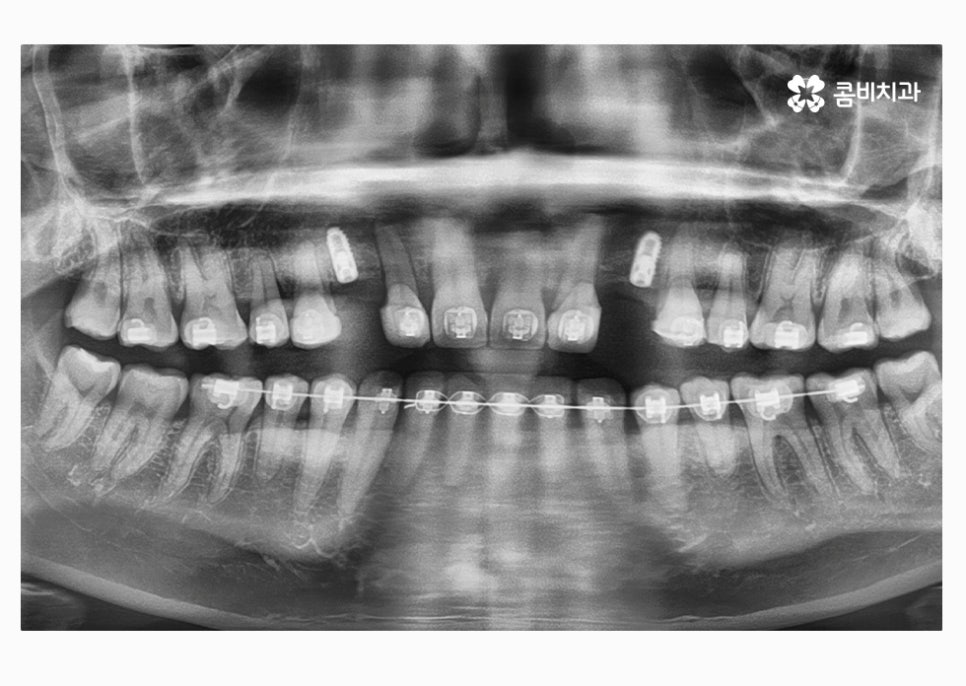

치아교정으로 치열을 가지런하게 하고

30대임플란트 식립까지 잘 마친 상태이며

식립 후에는 골 유착이 튼튼하게 이뤄지는지 기다린 후

주변 치아의 색과 모양에 맞는 보철물을 결합하여

마무리가 된다고 할 수 있어요.

앞니의 경우 심미적으로 중요하기 때문에 임플란트

치료에 있어서 식립 각도부터 보철물의 모양, 색 등

정확해야 하고 연세가 많은 분들의 경우에는